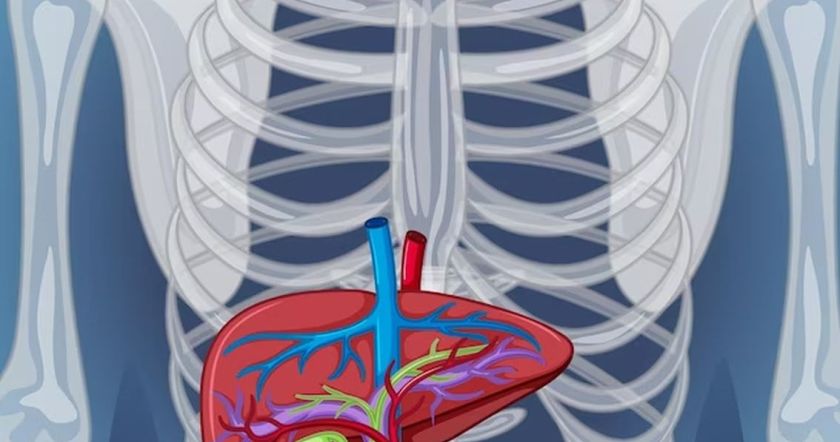

Врач Харлов отмети в интервью, что сегодня причиной возникающих проблем с печенью все чаще оказывается неправильное питание, а не злоупотребление алкоголем. Медик рассказал, в частности, что способствует развитию неалкогольной жировой болезни печени.

Дефицит белка и холина. Харлов подчеркнул, что для сохранения здоровья печени важно употреблять качественный белок животного происхождения – его недостаток ассоциируется с ожирением. Что касается холина (витамин В4), то дефицит этого вещества способствует стеатозу, поскольку именно от него зависит метаболизм в печени.

Растительные экстракты, антиоксиданты. Врач Харлов указал на токсичный эффект, который могут проявлять в отношении печени разные растительные экстракты. Многие антиоксиданты, употребляемые в большом количестве, разрушительно воздейтсвуют печень – например, органу вредит чрезмерный прием зеленого чая. Кроме того, для печени опасны кассия (растение, похожее на корицу) и гарциния (жиросжигающая растительная добавка). Все перечисленное может провоцировать развитие гепатита, предупредил специалист.

Лекарства. По словам специалиста, проблемы с печенью могут возникнуть после использования многих препаратов: в том числе эксперт назвал парацетамол, лекарства для терапии ВИЧ, противозачаточные с содержанием синтетических эстрогенов и другие.

Избыток железа, фруктозы. При слишком значительном накоплении железа могут развиваться опасные патологии печени в виде гепатитаа и цирроза. Также, подчеркнул гастроэнтеролог, для печени разрушительно большое количество искусственной фруктозы, получаемой с подслащенными продуктами.